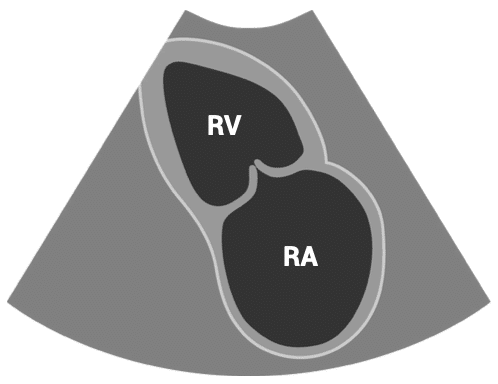

PARASTERNAL SHORT-AXIS (PSAX) VIEWS – PSAX aortic valve view

- Patient position: lying on left side, left arm raised, raise the back of the bed or use pillows under the left shoulder

- Probe position: 4th intercostal space, left sternal edge

- Probe orientation: notch towards patient’s left shoulder

Tilt probe upwards towards head to show aorta as a circle.